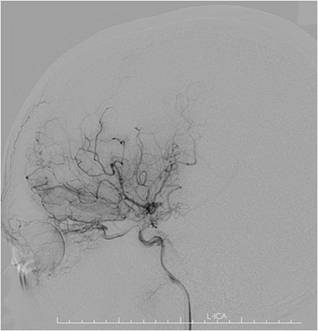

入院后,患者完善了所有检查;TCD提示:左侧大脑中动脉中度狭窄;右侧大脑中动脉血流减慢;左侧大脑前动脉及大脑后动脉血流速度增快;右侧大脑后动脉血流速度减慢。颅脑MRI-ASL提示:左侧额顶叶灌注低(如图2)。DSA影像显示:烟雾病(如图3)双侧颈内动脉末端闭塞,颅底可见烟雾状血管生成部分代偿供血。

图3,术前DSA可见颈内动脉末端闭塞